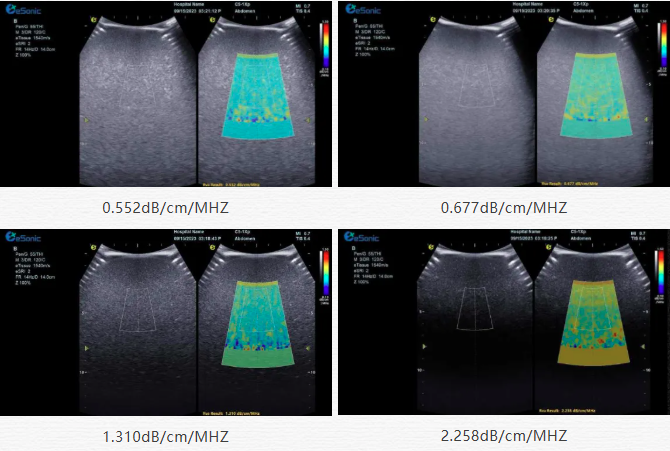

该技术基于声波在介质传播时的衰减,衰减由声吸收、反射、散射及波束扩散所致,声衰减系数(α,单位 dB/cm?MHz,与超声频率和传播距离成正比)可通过测定同频超声波在组织中的衰减程度,借回波信号分析预测声衰减系数或衰减率来评估组织特性。

目前市面常用瞬时弹性成像或仿体参照法,存在适用性、准确性差及无衰减图局限。银河官网则采用准确度更高的 ALA 幅度损失衰减法,超声波深度传播时回波幅度渐降,其对数与深度有良好线性关系,声衰减量与传播衰减系数成函数关系,调节取样框大小位置可实时得样框内组织衰减系数,用于定量评估病变程度。

声衰减定量成像技术的应用范围非常广泛,包括肝脏疾病、乳腺肿瘤鉴别、肾脏病变以及肌肉骨骼系统等多方面的病变。712a8084746869e803a3684e2526ee4.png肝脏疾病诊断在脂肪肝的评估中,脂肪作为一种声衰减介质,超声波在脂肪肝内的传播会产生衰减,肝脏中脂肪组织比例越大,超声衰减就越高。在肝硬化患者的肝脏中,肝脏组织的纤维化和结构改变会导致超声声衰减特性的改变。声衰减成像技术可以帮助医生观察肝脏实质的变化,辅助判断肝硬化的程度,同时对于监测肝硬化治疗过程中的病情变化也有一定的价值。